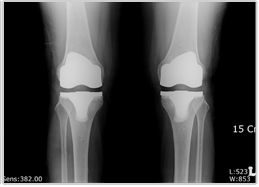

수술 전 수술 후

수술전 사진 수술후 사진